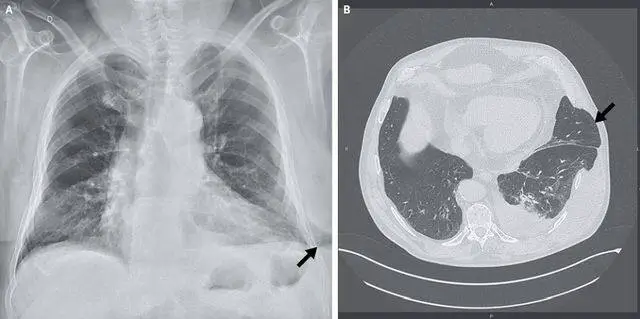

体查可见双侧胸壁不对称,肿胀部位可触及一柔软、可缩小的肿块,伴触痛。该肿块吸气时体积增大,呼气时体积减小。胸片可见单侧肺实质膨出于胸腔之外(图A,箭头所指)。CT检查可见左下肋间肺疝,伴左肺中度胸腔积液(图B,箭头所指)。

图.胸部影像学改变。胸片可见单侧肺实质膨出于胸腔之外(图A,箭头所指)。CT检查可见左下肋间肺疝,伴左肺中度胸腔积液(图B,箭头所指)。